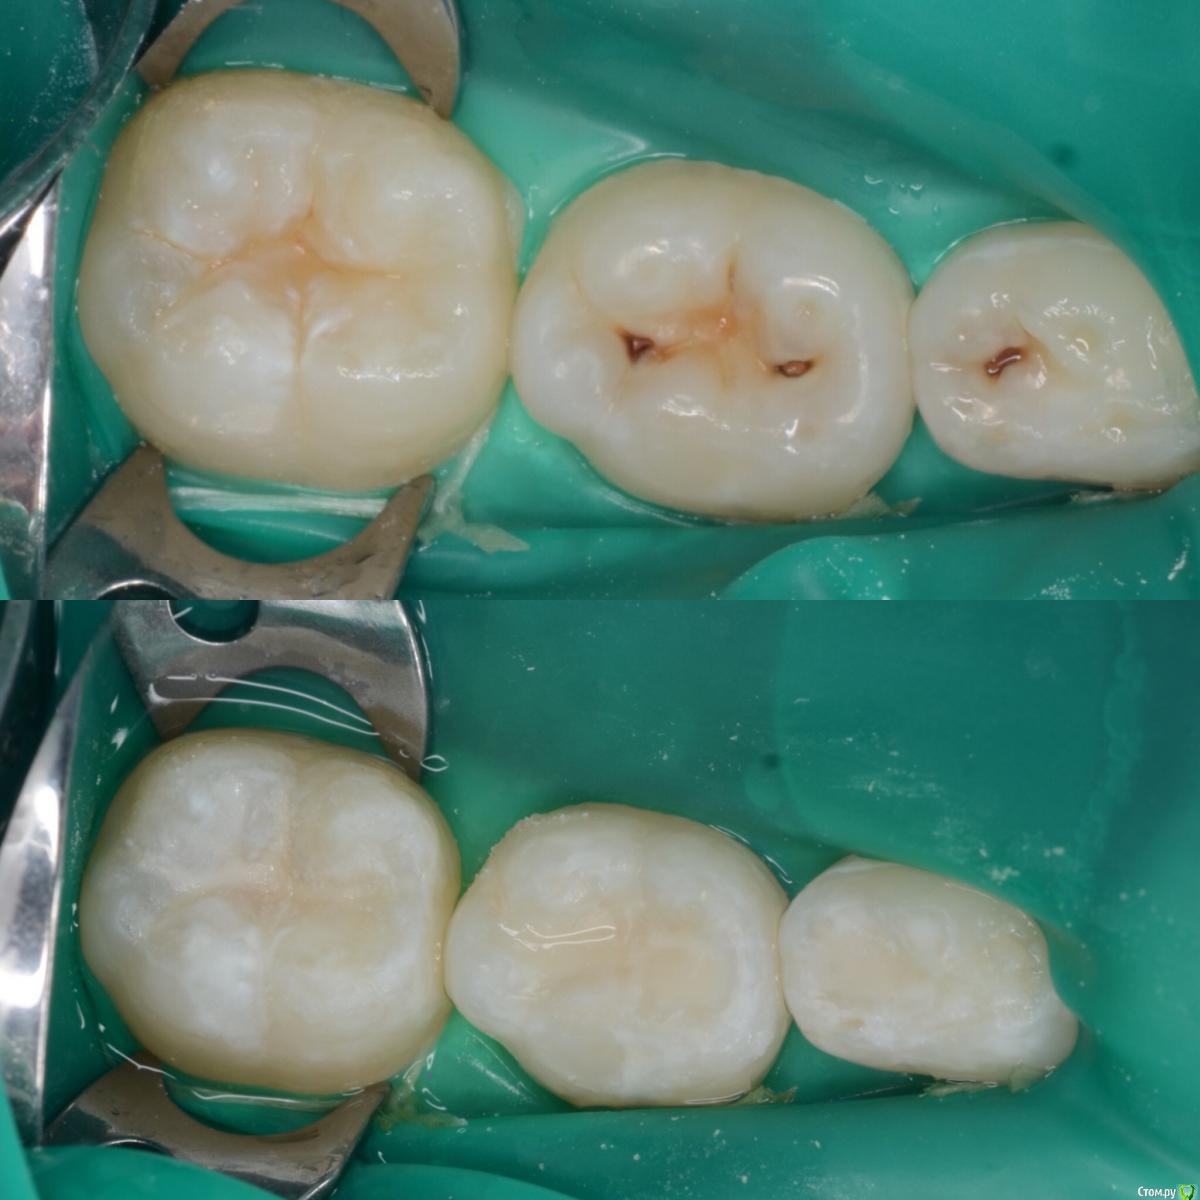

CRAZYDUCK Опубликовано 19 мая, 2018 Автор Поделиться Опубликовано 19 мая, 2018 Лечение кариеса 8.4 и 8.5 , герметизация 4.6 . 3 Ссылка на комментарий

CRAZYDUCK Опубликовано 19 мая, 2018 Автор Поделиться Опубликовано 19 мая, 2018 (изменено) Костя , 7 лет .Лечение кариеса 1.6; обратимый пульпит 5.4 и 5.5 .5.4 заполирован по контакту после снятия коффера, платок два раза меняла ( порвала по каоьакту). Фото после снятия коффердама уже не было сил сделать ;( ( новая ассистент, еще не сработались - дольше все делаем , чем с другим ассистентом .Ещё прийдет на лечение - сделаю . Изменено 19 мая, 2018 пользователем CRAZYDUCK 3 Ссылка на комментарий